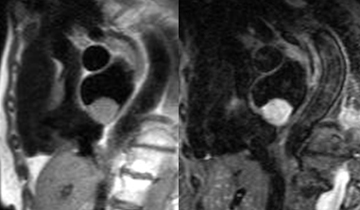

– Insuffisance tricuspide : intérêt de l’IRM dans la maladie d’Ebstein mais pas de quantification aisée de la PAP systolique comme en écho-doppler.

– Sténose pulmonaire : L’IRM aide à discriminer les atteintes valvulaires des obstacles sous ou sus valvulaires dans les cardiopathies congénitales.